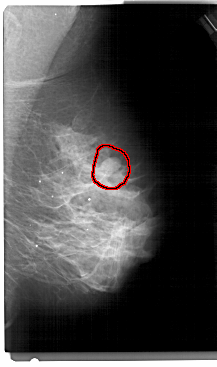

A_1305_1.LEFT_MLO

LEFT_MLO LINES 5491 PIXELS_PER_LINE 3211 BITS_PER_PIXEL 12 RESOLUTION 43.5 NON_OVERLAY

FILE: A_1305_1.RIGHT_MLO.OVERLAY

TOTAL_ABNORMALITIES 1

ABNORMALITY 1

LESION_TYPE MASS SHAPE OVAL MARGINS CIRCUMSCRIBED

ASSESSMENT 4

SUBTLETY 4

PATHOLOGY BENIGN

TOTAL_OUTLINES 1

BOUNDARY